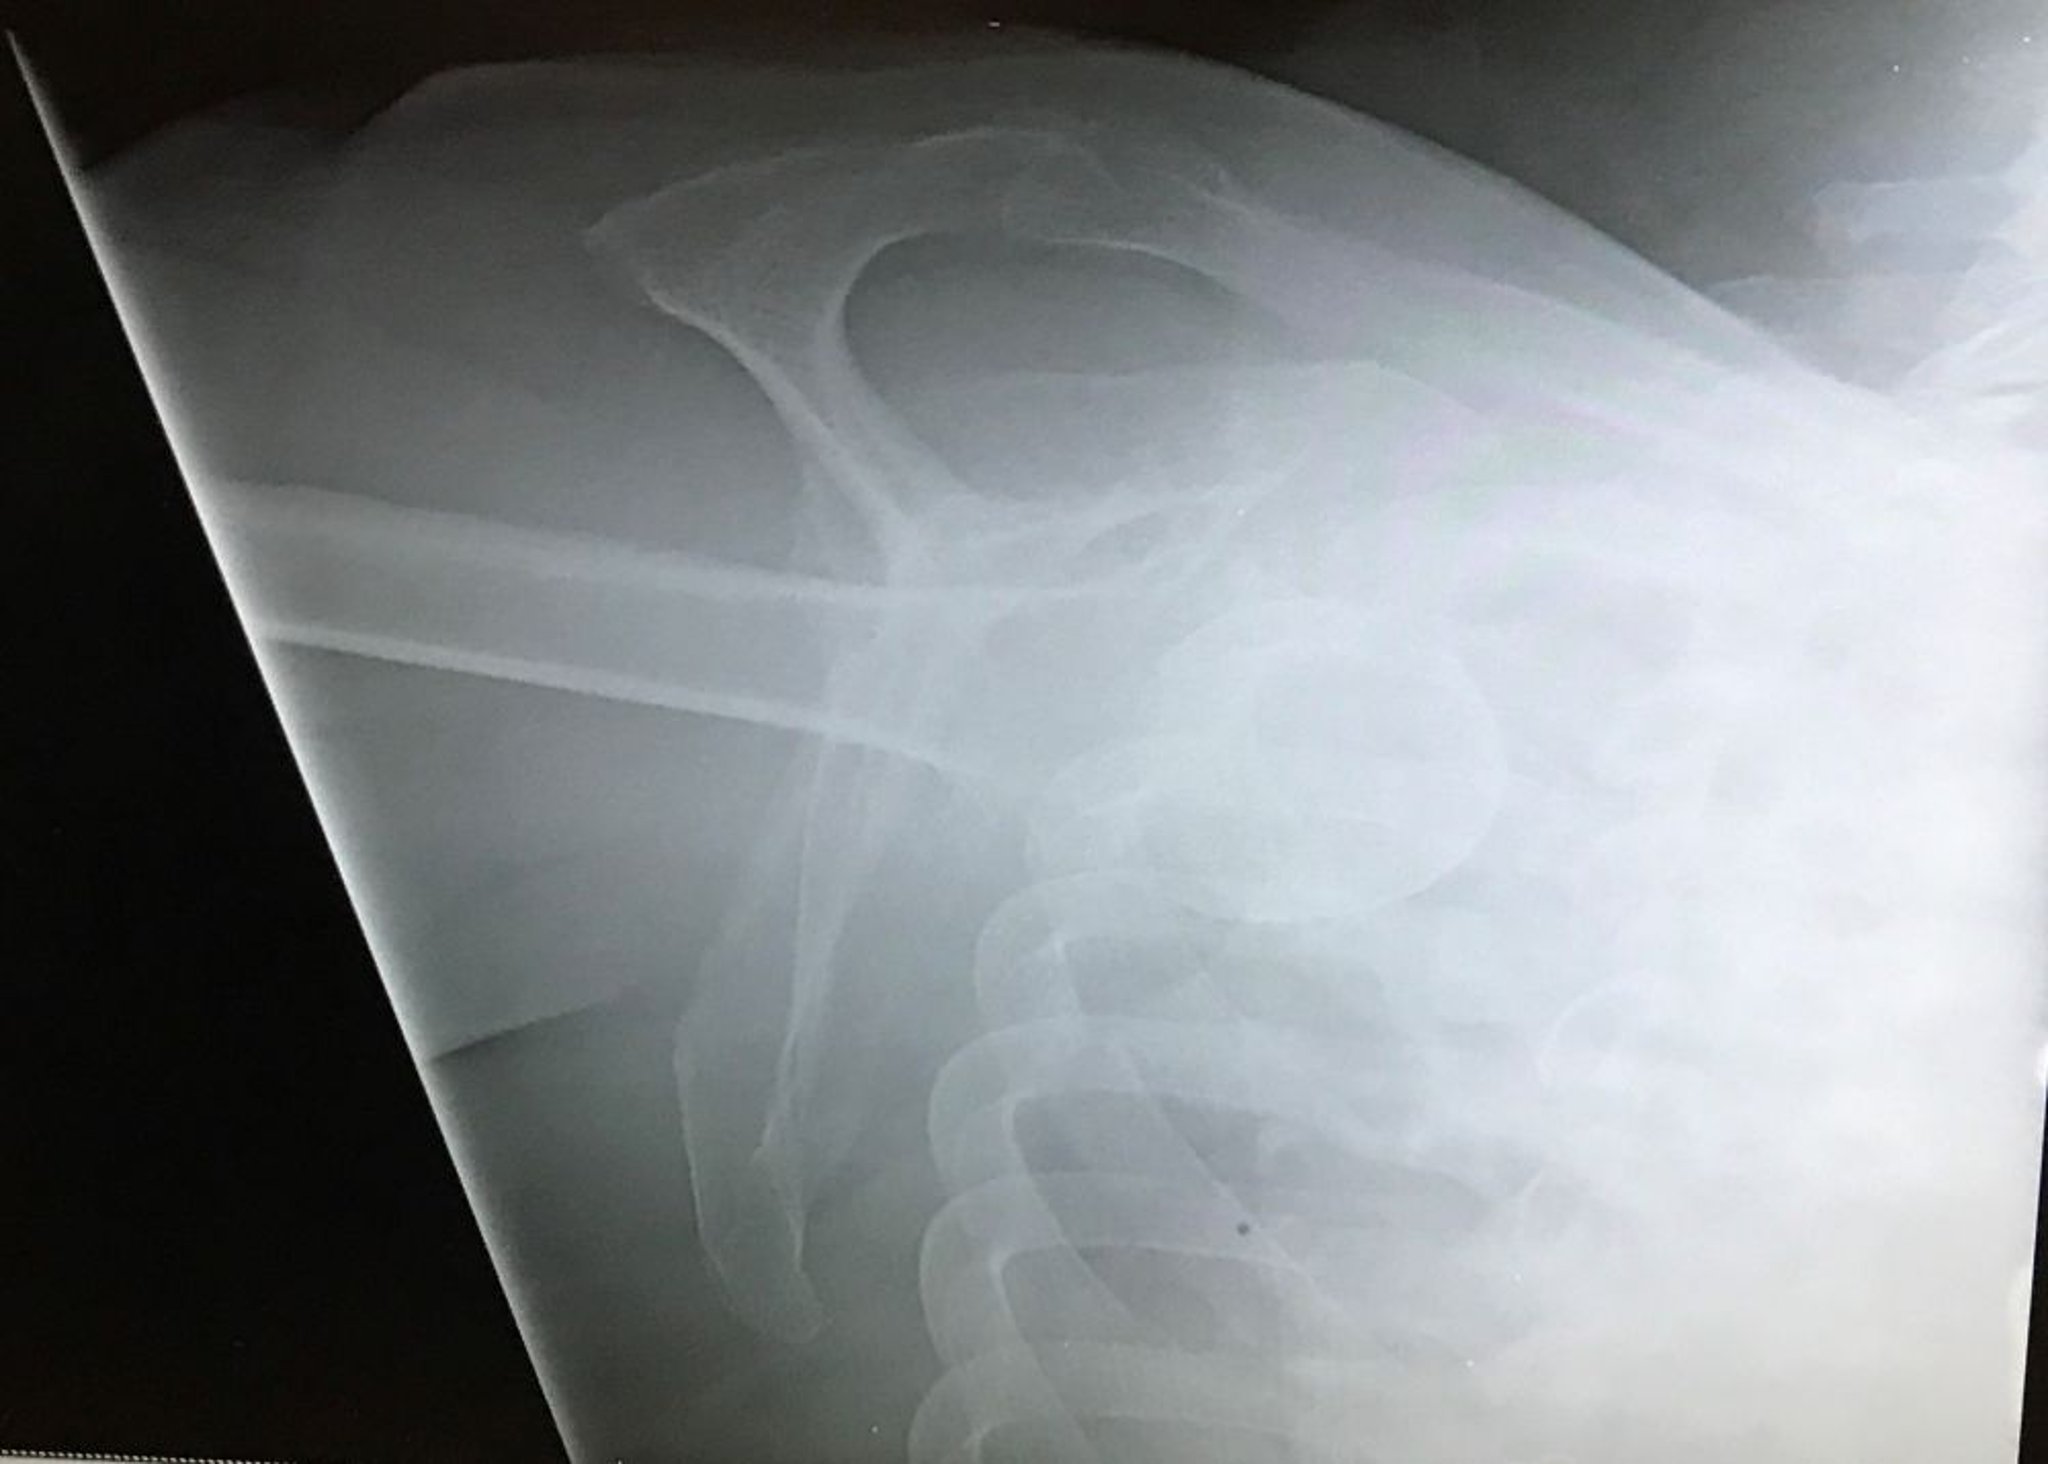

Нижний вывих плеча

На этой Y-проекции плеча показана головка плечевой кости ниже суставной ямки с конечностью, расположенной в проксимальном направлении, что указывает на нижний вывих плечевой кости (luxatio erecta).

Image courtesy of Danielle Campagne, MD.